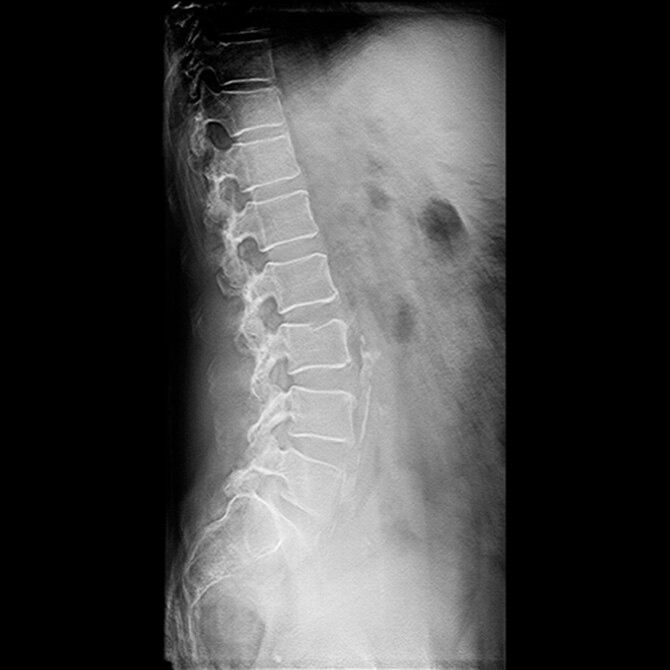

Consistent images

Harnessing AI for uncompromised image quality

Dual Energy Subtraction is delivered within the Helix™ advanced image processing chain, delivering improved consistency despite variations in exposure technique and challenging exam conditions.